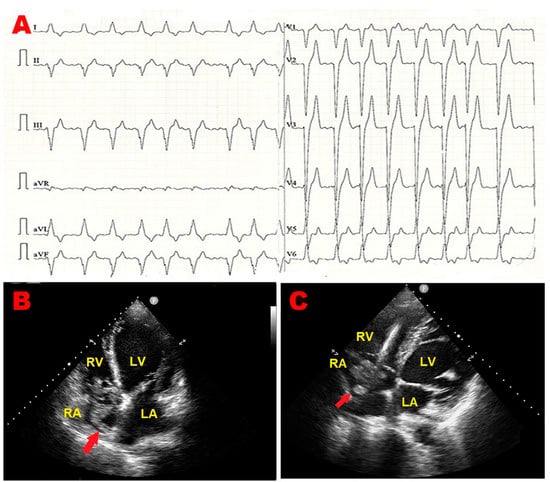

An 84-year-old male (BSA 1.63 m2, BMI 19 Kg/m2) was admitted to the emergency department of our institution due to fever, asthenia, and cough. As per past medical history, the patient was affected by chronic renal failure and ischemic dilated cardiomyopathy with reduced left ventricular ejection fraction (LVEF). He was previously implanted with a bicameral cardioverter–defibrillator. Upon physical examination, blood pressure was 126/79 mmHg, and heart rate was 123 b.p.m., with a body temperature of 38 °C. Arterial blood gas analysis revealed an oxygen saturation of 91%, pH of 7.43, mild hypoxemia (PaO2 = 76 mmHg), and normocapnia (PaCO2 = 35 mmHg). The electrocardiogram (ECG) detected atrial fibrillation (AFib) with left bundle branch block with rapid ventricular rate (Figure 1A). Blood tests showed neutrophilic leukocytosis [white blood cell count 43 × 109/L (range 4–11 × 109/L)], C-reactive protein of 22 mg/dL (range 0.05–0.50 mg/dL), and an estimated glomerular filtration rate of 18.5 mL/min/m2 with markedly elevated levels of D-dimer (>20,000 ng/mL) and N-terminal pro-B-type natriuretic peptide (NT-proBNP) (>10,000 pg/mL). An urgent TTE highlighted a large, S-shaped, and extremely mobile RA mass tethered to Chiari’s network, free-floating and prolapsing through the tricuspid valve into the right ventricle (Figure 1B–D). By placing a 5 mm sample volume of PW-TDI at the level of the mobile portion of the RA mass, a peak antegrade longitudinal velocity of 22.8 cm/s was recorded (Figure 1E). On PW-TDI, the RA mass showed a pattern of incoherent motion, with different velocities and directions compared to the surrounding myocardial tissue. Given the severe renal failure, contrast-enhanced chest CT could not be performed. Chest X-ray showed hilar congestion, multifocal pneumonia, and right pleural effusion (Figure 1F). The patient was hospitalized in the internal medicine ward. He was in poor general condition. Blood cultures and transesophageal echocardiography were not performed, and the patient was conservatively treated with anticoagulants (subcutaneous calcium–heparin 5000 I.U. every 12 h), intravenous (IV) antibiotics (piperacillin plus tazobactam 2.25 g every 8 h), IV diuretics (furosemide 40 mg/die), and beta blockers (metoprolol 150 mg/die). A follow-up TTE was performed after one week, demonstrating the complete resolution of the RA mass (Figure 1G). Accordingly, infective endocarditis was excluded, and the RA mass was judged to be compatible with a thrombus of the RA cavity entrapped within the Chiari network, which was promptly resolved through the use of antithrombotics. Despite the intense cardio-protective treatment, the patient’s condition quickly worsened, resulting in septic shock and death after two weeks of hospitalization.

Figure 1.

(A) Twelve-lead electrocardiogram, showing atrial fibrillation with left bundle branch block and rapid ventricular rate. (B) Transthoracic echocardiography. Apical four-chamber view, demonstrating a large, S-shaped thrombotic mass (red arrow) occupying the whole right atrial cavity. (C) Transthoracic echocardiography. Right ventricular focused apical four-chamber view showing the right atrial thrombotic mass (red arrow) between the Chiari network and the right ventricular lead. (D) Transthoracic echocardiography. Right ventricular focused apical four-chamber view showing the S-shaped right atrial thrombus tethered to Chiari’s network (red arrow), free-floating and prolapsing through the tricuspid valve into the right ventricle. (E) Pulsed wave tissue Doppler imaging is used to assess the right atrial mass mobility. Its motion was very rapid and uncoordinated, with increased peak antegrade velocity, measured by positioning the sample volume of pulsed wave tissue Doppler imaging on the free mobile portion of the mass. (F) Chest X-rays. Posteroanterior view showing hilar congestion, multifocal pneumonia, and right pleural effusion. (G) Transthoracic echocardiography. Right ventricular focused apical four-chamber view, revealing the complete disappearance of right atrial thrombotic mass. LA, left atrium; LV, left ventricle; RA, right atrium; RV, right ventricle; Va, antegrade velocity.